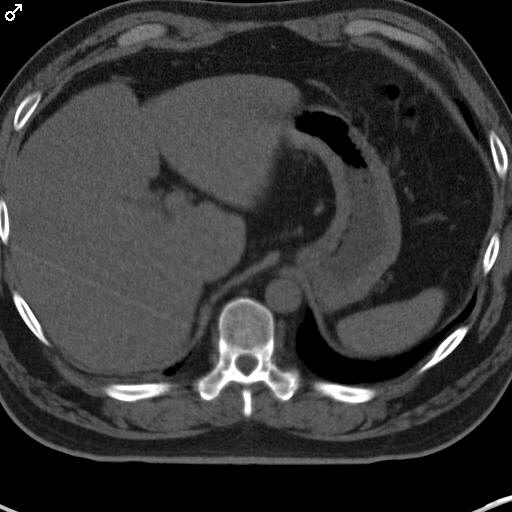

Tomografie computerizată abdomen, dreapta examinare cu SDC